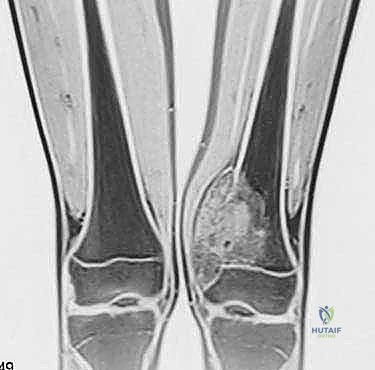

- الأشعة السينية (X-ray): الخطوة الأولى لتقييم العظام وتحديد نمط التدمير العظمي.

- الرنين المغناطيسي (MRI): هو المعيار الذهبي (Gold Standard) لتقييم الأورام. يوضح بدقة امتداد الورم في النخاع العظمي والأنسجة الرخوة، وعلاقته بالأعصاب والأوعية الدموية.

- الأشعة المقطعية (CT Scan): ضرورية لتقييم القشرة العظمية والتكلسات داخل الورم، وللبحث عن أي انتشار في الرئتين.

يعتمد الأستاذ الدكتور محمد هطيف على دراسة هذه الصور الإشعاعية شخصياً قبل تحديد مسار إبرة الخزعة، لضمان عدم تلويث الحجرات العضلية السليمة (Compartments).

الحالة الأولى: إنقاذ ركبة رياضي شاب

شاب يبلغ من العمر 19 عاماً عانى من ألم مستمر في الركبة وتورم لم يستجب للمسكنات. بعد الفحص السريري الدقيق وإجراء الرنين المغناطيسي، اشتبه الأستاذ الدكتور محمد هطيف بوجود ورم. تم إجراء خزعة إبرة أساسية دقيقة جداً. أظهرت النتائج وجود "ساركوما عظمية" في مراحلها الأولى. بفضل الخزعة الدقيقة التي لم تلوث الأنسجة المحيطة، تمكن الدكتور هطيف لاحقاً من استئصال الورم بالكامل وتركيب مفصل صناعي خاص بالأورام، مما أنقذ ساق الشاب من البتر ومكنه من العودة للمشي بشكل طبيعي.